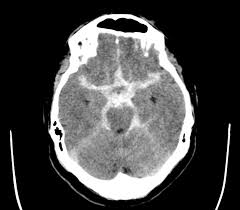

الintra-cerebral سببه ضغط عالي(هتلافي فوق ال200) مشهور في الbasal ganglia وهتلاقي معاه ضعف او تنميل نص الجسم

وال3 اي اعمي بيشوفهم في الاشعة

27- في بقي نوع خبيث بتلاقي كل الcistern مفتوحة زلفل بس في الsulcus تحت بقي فيه خط ابيض ، او نقطة دم في قاع الlateral venrticles

لو مش عينيك في وسط راسك سهل جدا انك تmiss عيانSAH

لازم تتاكد ان كل الcisterns - ventricles والsulci مفتوحة وفيها csf اسود

28- ع الناحية التانية ، في ناس بتتلخبط بين calcification الdura وتقول عليه دة دم جوا الcistern

وناس اروش بتتلخبط بين الcalcification بتاع الchoriod plexus وتقول عليه دم جوا الventricles

انا قعدت شهور عشان اتقن منظر الsubarachnoid في الاشعة